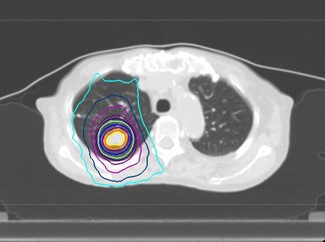

当科では治療用のCT(富士フィルム SCENARIA64列)、3次元治療計画装置(Ray Search社 Ray Plan)、ライナック(ELEKTA社 Precise Treatment System)が設置されています。CTシミュレーターを用いた3次元治療計画を行い、多方向から病巣へ線量を集中させて最大限の効果をねらうと同時に、周囲臓器への被曝を減らして副作用を最小限に止めるよう努めています。

肺がんに集中した3次元治療計画の線量分布図